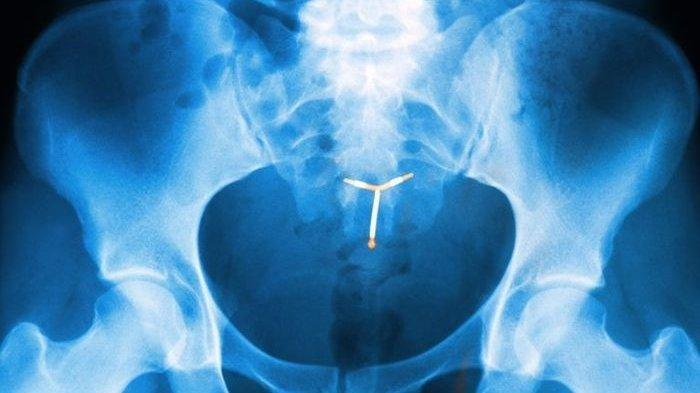

Jayne tak bisa punya anak karena KB IUD tertinggal di tubuhnya selama 29 tahun.

Pada tahun 1990, Jayne Huddleston diberitahu oleh dokter umum bahwa IUD yang dia pasang sekitar setahun sebelumnya telah lepas.

Pada saat yang sama, Jayne memutuskan untuk memasang KB IUD lagi.

Namun, dua tahun kemudian, dia dan suaminya David, 61, memutuskan untuk memiliki anak, jadi mereka melepas IUD kedua.

Karena KB IUD pertama masih ada di tubuhnya, selama bertahun-tahun tanpa disadari.

Jayne menderita gejala tidak nyaman termasuk menstruasi yang berat, pendarahan, sakit perut, dan infeksi.

Secara khusus, dari tahun 1995 hingga 2002, pasangan tersebut tidak dapat hamil meskipun telah melalui delapan upaya fertilisasi in vitro.

Saat CT scan, KB IUD tersisa di tubuh Jayne ditemukan oleh dokter.